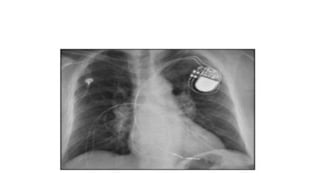

8.

Atrial lead dislodgment to ventricle

12.60 yr old male with cardiogenic shock

xray taken after cardiac intervention

- The end of the balloon should be just distal (1-2 cm) to the takeoff of the

left subclavian artery

iabp ballon positioning